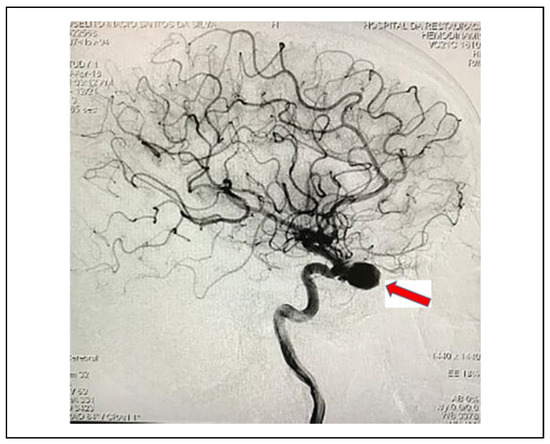

Pseudoaneurysm of the Internal Carotid Artery After Craniofacial Traumatism: Series of Cases and Integrative Literature Review

by Priscilla Sarmento Pinto, Ruan de Sousa Viana, Rosa Rayanne Lins de Souza, João Luiz Gomes Carneiro Monteiro and Suzana Célia de Aguiar Soares Carneiro

Craniomaxillofac. Trauma Reconstr. 2021, 14(4), 330-336; https://doi.org/10.1177/1943387520980946 - 14 Dec 2020

The present study aims to develop an integrative review about pseudoaneurysms after traumatic facial trauma, through the analysis of its etiology, type of fracture, signs and symptoms, time elapsed between the trauma and the exposure of signs and symptoms, and treatment performed in [...] Read more.

The present study aims to develop an integrative review about pseudoaneurysms after traumatic facial trauma, through the analysis of its etiology, type of fracture, signs and symptoms, time elapsed between the trauma and the exposure of signs and symptoms, and treatment performed in these cases. Furthermore into the report, there are 3 clinical cases that occurred in the Buccomaxillofacial Surgery and Traumatology service of Hospital da Restauração Recife/PE. The study was carried out in 2 phases, first, a digital research about post-traumatic craniofacial pseudoaneurysm was performed in the following databases “MEDLINE/PubMed,” “Scielo” and “Scopus,” in September 2019, with 5 articles being included. In the second, 3 cases of patients with high-impact facial trauma who developed pseudoaneurysm of the internal carotid artery were reported. The average age of the patients was 35.6 years, all patients were male (100%), the majority (60%) being victims of an automobile accident, 3 patients (60%) suffered craniofacial trauma and 2 (40%) had trauma only to the face, most of them had symptoms later on due to the trauma, in 80% of cases the therapy instituted was embolization. Cases of high-impact craniofacial traumas, which present epistaxis and/or ophthalmological alterations correlated to fractures, should be carefully evaluated, determining a better prognosis for the patient. Full article